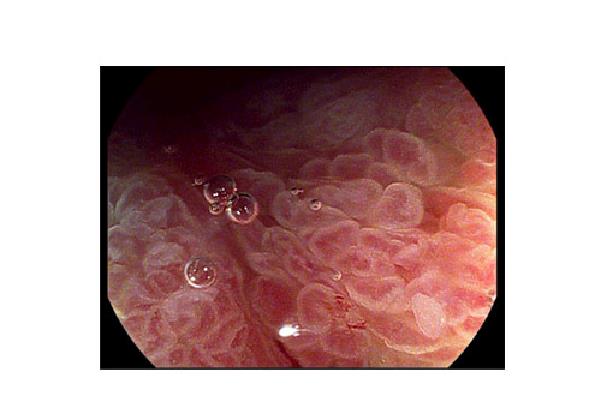

Med Pentax’ nye, unikke MagniView gastro- og koloskoper får du et fantastisk billede i fuld HD+-opløsning med en trinløs optisk 165x zoomfunktion (146x i kombination med en 26" monitor og 165x i kombination med en 32" monitor). I kombination med i-scan sættes en helt ny standard for den daglige praksis, når det gælder mulighederne for at stille den rigtige diagnose.

MagniView er bygget på Pentax’ 90-serie og er i bund og grund et helt almindeligt skop med den samme ydre diameter som standard diagnostiske endoskoper – bare med zoomskopets nye muligheder. Skopet har 90-seriens gode ergonomi, er let at positionere og har en let anvendelig zoomfunktion, som betjenes fra drejehåndtaget via tommelfingeren.